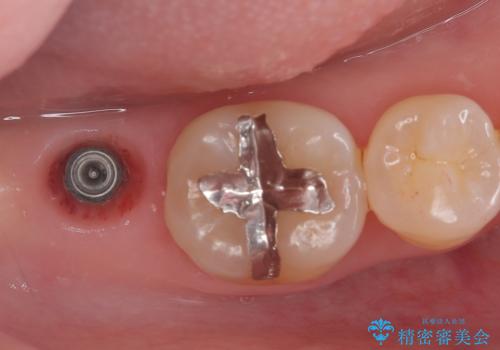

矯正の治療も進めながら、インプラントを埋入して補綴をおこなっています。

骨幅があったため、太いインプラント体を使用しています。

今回はスクリューリテインにて修復を行なっています。